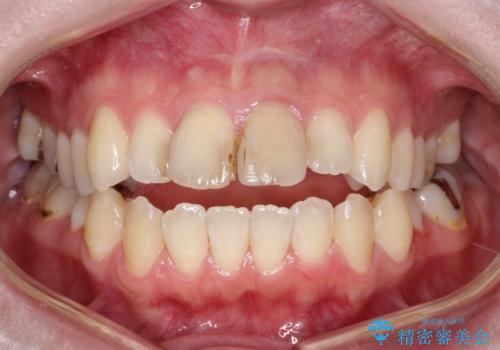

前歯の色が気になる【オールセラミッククラウン】

- 「前歯の色が気になる」を主訴に来院された患者様です。前歯が咬んでない開咬という状態のため、矯正治療を勧めましたが、患者様がご希望されなかったためオールセラミッククラウンで治療を行いました。右上1番は、神経の検査の結果、神経が死んでいたため根管療から行いました。左上1番は、金属の土台が入っていたのとラバーダムシートを使用せず根管治療が行われていたため、再度根管治療から行いました。その後ファイバーコアをたてオールセラミッククラウンで治療を行いました。

※今後ホワイトニングを行う予定なので患者様の希望により少し被せ物を白くしています。